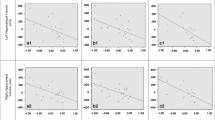

Table 1 displays descriptive statistics for all study variables. Childhood maltreatment was endorsed by 58% of mothers, with 54.4% (n = 31) experiencing one or more forms of abuse, 28.1% (n = 16) experiencing one or more forms of neglect, and 28.1% (n = 16) experiencing both forms of maltreatment (categories not mutually exclusive). Infant age at MRI was strongly positively correlated with GMV (r = 0.81, p < 0.001; Fig. 1), but not other brain volumes (rrange = 0.13 to 0.20, all p n.s), consistent with the rapid growth in GMV over the first two years of life (Gilmore et al., 2012). Potential covariates, including annual household income, maternal education, maternal depressive symptoms, infant sex, infant minority status, and gestational age at birth were assessed in relation to infant brain volumes. Higher maternal depressive symptoms were associated with larger infant left hippocampal volume (r = 0.28, p < 0.05). No other potential covariates were associated with infant brain volumes (rrange = -0.04–0.25, all n.s.). Although sex was not significantly associated with brain volumes, given sex effects documented at older ages (Gilmore et al., 2018), sex was controlled in all analyses. Thus, all analyses included infant age at MRI and infant sex. In addition, depression was included as a covariate in left hippocampal analyses. Lastly, due to rapid brain growth over this age range, all models assessed whether the relation between type of maltreatment and brain volume was moderated by age.

Infant GMV

To evaluate the independent contributions of MCNeglect severity and MCAbuse severity to infant GMV, the regression model included both MCNeglect severity and MCAbuse severity, with infant age and sex controlled. Consistent with Hypothesis 1, when both types of maltreatment were included in the same model, only MCNeglect accounted for significant variance in infant GMV (see Table 2). These results indicate that severity of maternal childhood neglect made an independent contribution to reduced infant GMV, whereas maternal childhood abuse did not explain additional variability in infant GMV with neglect controlled. Neither the MCNeglect by age interaction nor the MCAbuse interaction terms were significant for GMV (Table 2). These findings suggest that the association of MCNeglect severity with lower GMV was similar across the first two years of life. The slopes of the effects of maternal childhood neglect and abuse on residualized infant GMV are shown in Fig. 2a, b.

Infant grey matter volume in relation to severity of maternal childhood neglect (a) and abuse (b). Note. N = 57. Residual values for GMV after controlling for age, sex, and the other type of maltreatment (abuse or neglect). Y axis indicates deviation from GMV mean score; X axis indicates deviation from ACE mean score. Maternal childhood neglect β = -0.20, SE = 0.09, 95% CI [-0.38, -0.02]; maternal childhood abuse β = -0.05, SE = 0.10, 95% CI -0.23 – 0.14]

Infant Amygdala Volume

Using similar regression models for infant right amygdala volume, there was no main effect of MCNeglect severity nor interaction effect of MCNeglect severity by infant age (Table 2). However, consistent with hypotheses, there was a significant interaction between MCAbuse severity and infant age, such that MCAbuse severity was associated with reduced infant right amygdala volume at older ages (Table 2). Analysis of the region of significance for the age by MCAbuse interaction indicated that infant right amygdala volume was reduced in relation to MCAbuse severity after 18.0 months of age (older than 548.65 days; Johnson & Neyman, 1936; see Fig. 3).

Region of significance of the interaction between severity of maternal childhood abuse and infant age at MRI on infant right hemisphere amygdala volume. Note. Region of significance plotted using the Johnson-Neyman method (Johnson & Neyman, 1936). Graph derived using linear regression with MLR estimation, without FIML. N = 56 (one outlier removed). When infant age is outside the interval [-102.35, 548.65 days], or 18 months, the slope is significant, p < 0.05